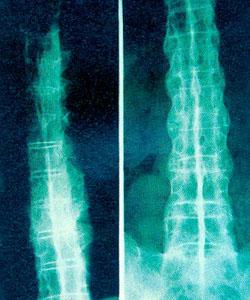

而当我们坐着时,腰背肌肉一直紧绷着,上身的重量都压在了腰椎骨和臀部上,久而久之就易造成腰部软组织和腰椎的积累性损伤,出现腰肌劳损、腰椎间盘突出等症状。

长时间的体力劳动、身体长时间维持一个姿势、腰部不注意保暖、急性损伤处理不当等都会引发腰肌劳损。长期伏案工作、需要久坐的人最容易患腰肌劳损,比如文案、司机等等。